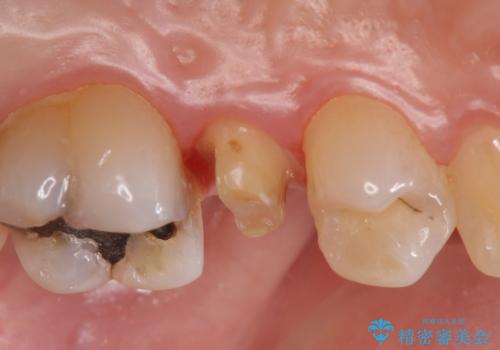

- 左上5番目の歯がしみるといらっしゃった方の症例です。

頬側の樹脂及び銀歯を除去後、オールセラミッククラウンにて補綴を行いました。